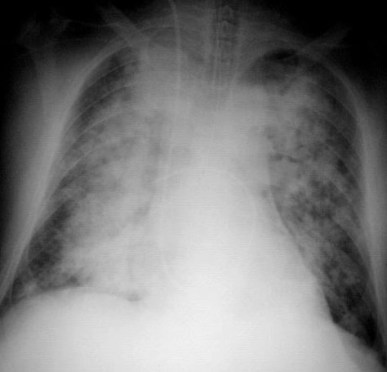

SIGNO DE LAS ALAS DE MARIPOSA

Signo de condensación alveolar bilateral en la radiografía posteroanterior (o anteroposterior) de tórax, propio del edema de pulmón de cualquier causa, aunque también puede verse en neumonías por gérmenes no habituales y hemorragia pulmonar. El signo recibe este nombre por la disposición perihiliar y simétrica de los infiltrados, que respetan la periferia pulmonar.

También se denomina signo de las alas de murciélago, pero está más extendido el término «alas de mariposa», que es, además, más gráfico.

La radiografía de este paciente con edema agudo de pulmón, muestra además, un tubo endotraqueal y un catéter de Swan-Ganz para medir las presiones de la arteria pulmonar.